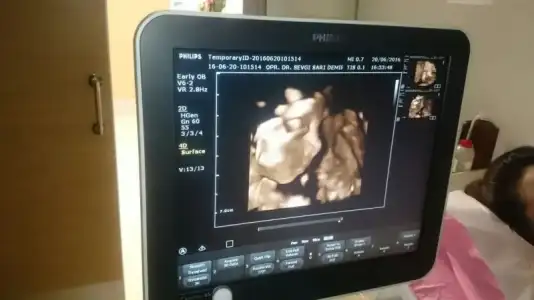

İyi akşamlar kızlar doktora gittik bugün kızım 671 gram 30 cm olmuş :) herşey yolunda dedi doktor çok şükür :) yarında kan ve idrar tahlillerim yapılacak inşallah onlarda temiz çıkar. Kızım ultrason görüntüsünde yine işaret parmağıyla ultrasonda birşeyler anlatmak istiyor gibiydi her doktora gitmemizde işaret parmağıyla mutlaka bi pozu oluyor :)